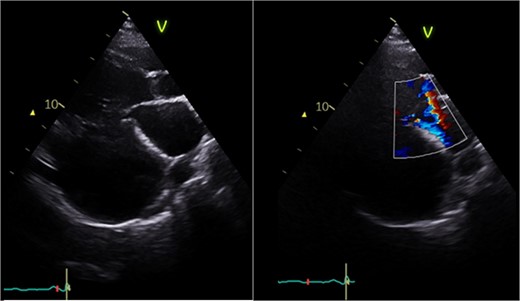

The heart was deaired and pacing wires placed. Despite successful initial weaning from cardiopulmonary bypass (CPB) with support (dopamine, adrenaline, noradrenaline), repeat pharmacological intervention was necessary. Central veno-arterial extracorporeal membrane oxygenation (VA-ECMO) was established by exchanging bicaval cannulae for a two-stage venous drainage cannula and utilizing the existing aortic cannula. Flows of 4–5 L/min were maintained, and the heart continued to eject with aortic valve opening. The patient was transferred to intensive care in a stable condition and recovered on ECMO for 6 days before decannulation and chest closure 48 h later. Following medical optimisation, he was discharged on postoperative day sixteen. Postoperative echocardiography (Fig. 6) revealed LV improvement (LVEF 45%) with a competent MV (trace regurgitation, no stenosis). At 1-year follow-up, the patient was recovering well without complications with preserved ejection fraction and mild residual MR.

Postoperative echocardiography: restoration of mitral valve leaflet coaptation and LV geometry, resulting in trivial regurgitant jet.